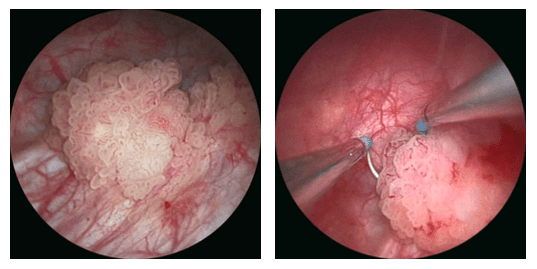

| La técnica de resección de la vejiga fue descrita por Nesbit en el año 1943. |

Las lesiones grandes deberían ser resecadas en varios tiempos enviandose muestran separadas para el estudio. Se dará información detallada de cada frasco en el cual se deberá identificar la base tumoral y según las guías incluso los bordes de la lesión.

La extensión de la lesión debería alcanzar un margen de al menos 2 cm, debido a que evidencia anatomopatológica, demuestra que el crecimiento tumoral puede alcanzar esta distancia de penetración lateral. ***

En principio toda resección debe realizarse en profundidad hasta por lo menos alcanzar la grasa que se ve entre las fibras musculares y el tejido perivesical. ***